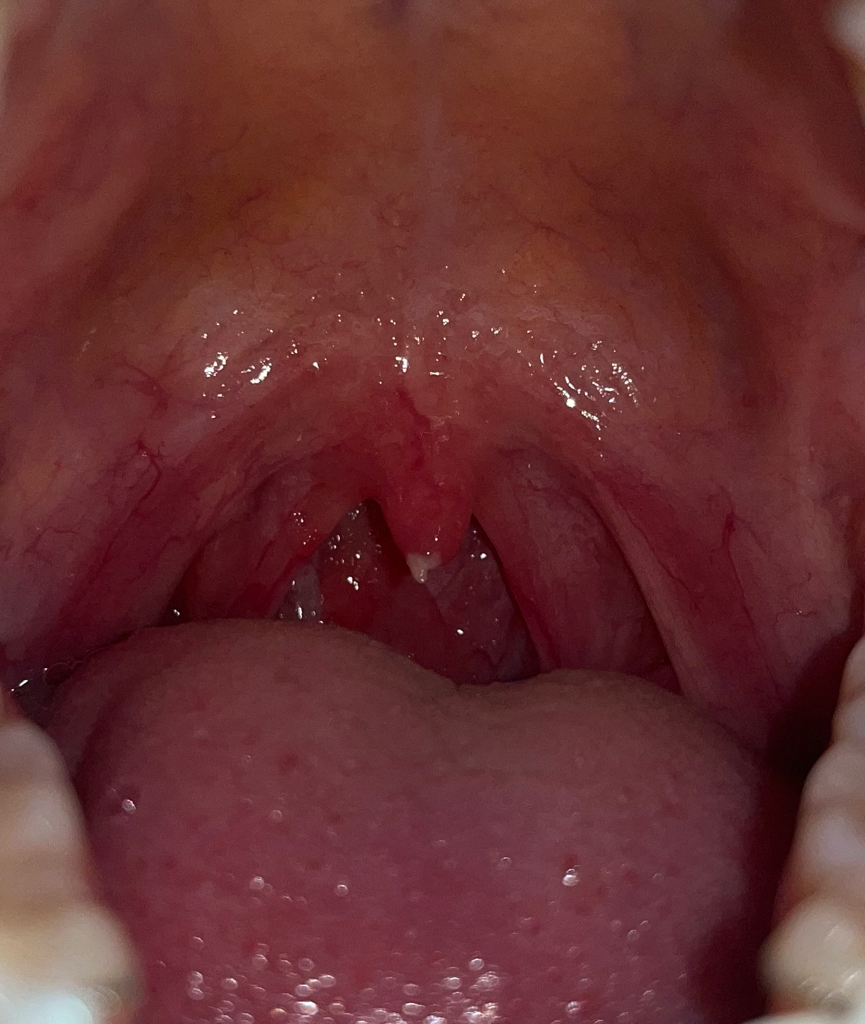

목에 이물감이 느껴져서 보이까 목젖에 뭐가 생겼어요

오늘 목에 이물감이 느껴져서 입 벌려서 거울을 보니까 목젖에 뭐가 생겼더라고요.

어제부터 오늘까지 아침쯤에만 침을 넘길때 목이 살짝 아프다는 느낌을 받았었는데 관련이 있을까요..

뭔가 떨어질 것 같은데 손으로 뜯으면 당연히 안되는거겠죠?ㅠㅠ저 괜찮은걸까요..

목젖이 있는 부위에는 결석등이 생길수도 있습니다.

결석이 생기게 되면 냄새가 나고 이물감이 느껴질수 있습니다.

자세한 확인을 위해서 이비인후과에서 진료를 받아보세요.

편도가 부으신거 같은데 치과보다는 이비인후과를 가셔서 검진을 받아보시는게 좋을것같습니다.

목 주위에 생긴 염증으로 보여집니다. 최근에 컨디션이 안 좋았거나 호르몬 등의 영향으로 나타날 수 있을 것으로 보입니다. 다만 대부분의 이러한 양상은 2주 안에 회복되나 불편감이 크거나 2주가 지났어도 증상이 나아지지 않는다면 치과나 이비인후과 방문이 필요합니다.